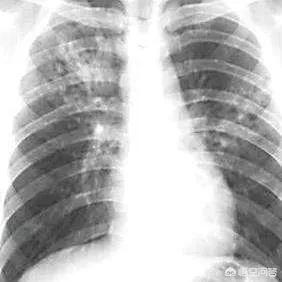

1.結核

2015年現在、約39万人のHIV感染者が結核で死亡している。結核はアフリカでHIVとともに生きる人々の死因の第1位であり、世界的にもHIVとともに生きる人々の死因の第1位である。症状には発熱、寝汗、咳、痰などがある。

- TB

結核はAIDSと同時に発症することもあれば、AIDSの前に発症することもある。AIDSの後期になると免疫が破壊され、潜伏していた結核菌が活性化し、結核を引き起こす。主な臨床症状は、発熱、咳、痰、喀血、寝汗、体重減少、食欲不振である。大まかな統計によると、HIV感染者の15%が結核を発症する可能性がある。